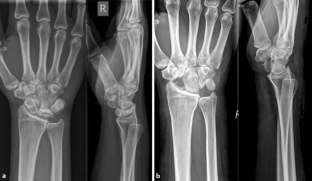

Abb. 1